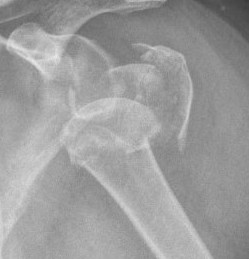

Four part

Avascular necrosis (AVN)

In most fractures, arcuate artery is disrupted, but head survives

- posterior circumflex artery is sufficient

- risk increases with amount of displacement

- 4 part fracture 30%

- 3 part fracture 15%